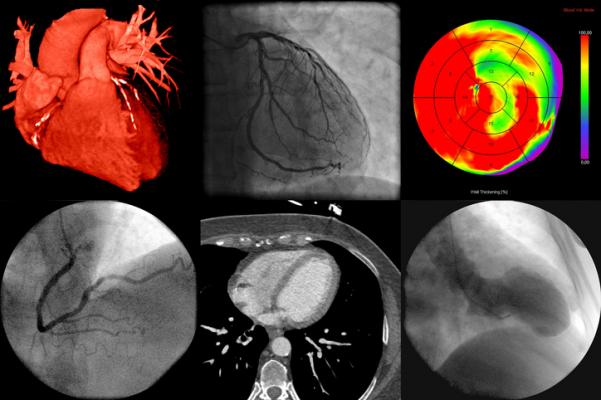

September 28, 2021 — A new study published in Radiology: Cardiothoracic Imaging on cardiac imaging trends over a decade reports that the rate of coronary computed tomography angiography (cCTA) exams by radiologists in hospital outpatient departments increased markedly from 2010 to 2019, suggesting a bright future for the technology. The study also found that reimbursement cuts and advances in technology have helped shift much of the imaging done by cardiologists from the office to hospital outpatient department.

Imaging has long played a critical role in the diagnosis of cardiovascular disease, the leading killer in the world. Both radiologists and cardiologists perform noninvasive cardiac imaging, but over time two of the most common cardiac imaging methods, echocardiography and myocardial perfusion imaging, became almost exclusively the domain of cardiologists.

During that same period, technological advances made competing imaging exams traditionally performed by radiologists, such as cCTA, appealing options.

Over the same period, the rates of cCTA by radiologists in hospital outpatient departments increased by 355%. Overall rates, however, remained low compared to myocardial perfusion imaging, despite the fact that some studies have shown cCTA to be more accurate. The technology’s uptake may be limited, Reeves said, by its complexity and the cost of equipment, in addition to the fact that it requires a dedicated technologist.

“Coronary CTA is a useful screening tool for coronary artery disease that obviates the need for invasive coronary angiography,” Reeves said. “I think the future is looking favorably on it.”